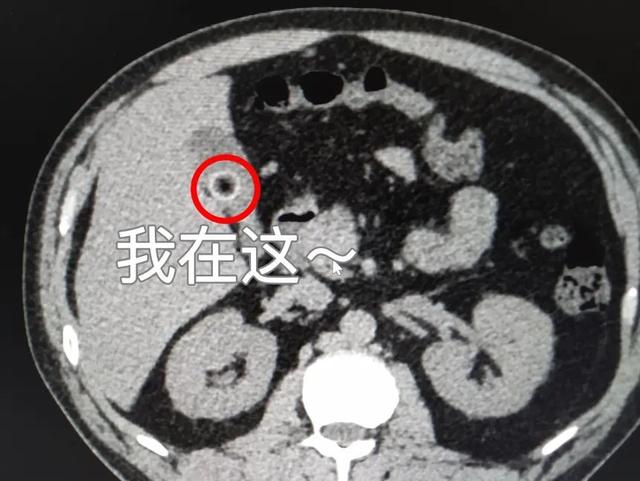

然而急查腹部ct提示关爹爹的胆总管下段结石,胆囊结石伴慢性胆囊炎

图片尺寸575x388